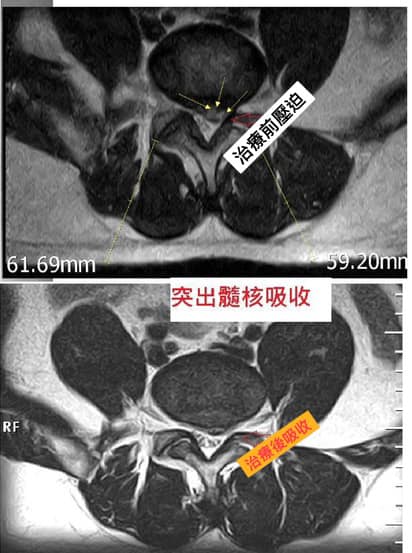

🌐結果:從10/9-12/26治療快十周總共十次,前三次次效果就很明顯,走路疼痛下降很多,到一月中時安排患者再拍攝一次MRI,把縱切面跟橫切面盡量調到同一張角度,比較後發現髓核有吸收現象。